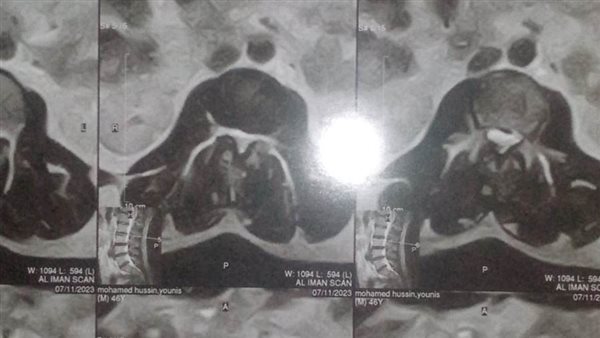

عم محمد راجل بسيط يبلغ من العمر 48 عاما مصابا بلانزلاق الغضروف بفقرات القطنية الرابعة والخامسة والعجزية اولي منذ 11عاما يستغيث بالمسؤولين والتأمين الصحي وأهل الخير لإنقاذه ومساعدته للحصول على العلاج حيث يقول إنه من سنة زاد عليه الألم وتوقف عن العمل نهائي وليس له تأمين صحي ولا معاش يستطيع منه الصرف على العلاج وأنه بسبب الألم المتكرر وتنميل بالقدم واصيب بتشنج بالأعصاب الطرفية بسبب إصابته بالسكر بدم ومؤخرا بضغط واكتئاب نفسي.

عم محمد يقول ذهبت لأكثر من دكتور مخ وأعصاب منهم قال لا بد من تدخل جراحي لاستئصال الغضاريف ومنهم قال أدوية وراحة تامة وللأسف 10 شهور مافيش نتيجة وتعبت من المسكنات والحقن وآخر دكتور قال عدم مجهود نهائي لأن متوقع انفجار الغضاريف والحالة متأخرة اسكن بالإيجار الجديد وعليه ديون الإيجار متراكمة من 8 أشهر بمبلغ 7000 جنيه غير فواتير الكهربا والغاز والمياه وأقيم بمفردي بعد الانفصال ووفاه أبي وأمي رحمهما الله،،